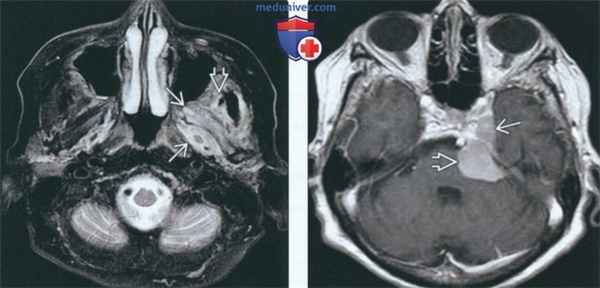

(Слева) На аксиальной МРТ (Т2 ВИ FS) определяется гиперинтенсивный сигнал в отечных мышцах (крыловидной и височной), свидетельствующий об острой - подострой денервационной атрофии.

(Справа) На аксиальной МРТ (Т1 ВИ С+) у это го же пациента визуализируется менингиома в области кавернозною синуса и предмостовой цистерны, ставшая причиной денервации.